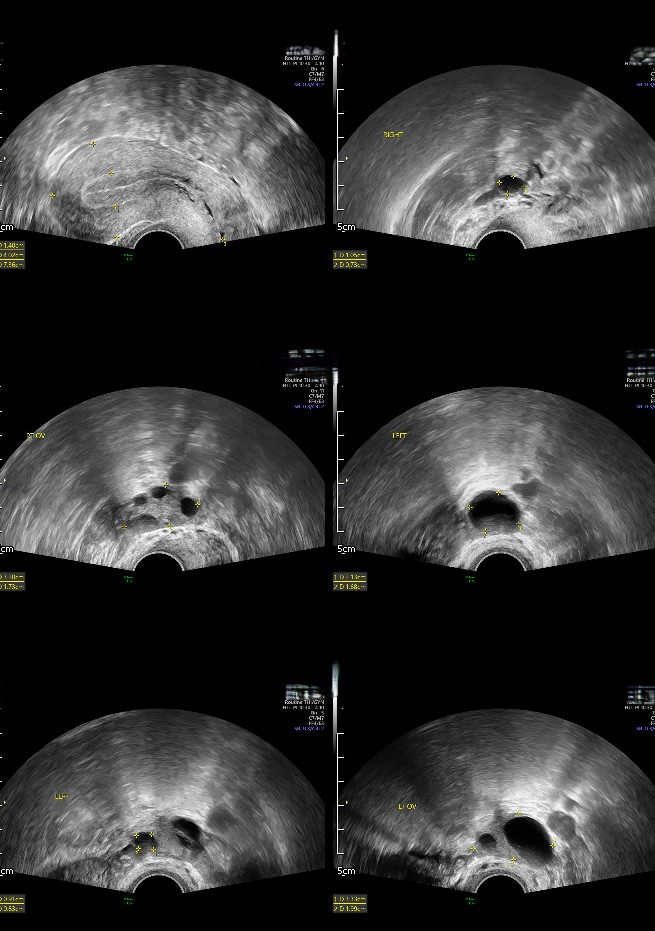

每次她躺在超音波檢查台上,眼睛注視著螢幕,心情總是既緊張又充滿期待。醫生告訴她,卵巢的情況不錯,兩側都能見到發育中的卵泡。接著在醫師的指導下,夫妻倆進行了排卵誘導後的夫妻同房。幾個星期後,她的心跳得比平常快許多,因為檢驗結果顯示K小姐懷孕了!K小姐說,那是一種無法形容的喜悅,這是她期待已久的孩子。關關難過關關過,事事難成事事成

命運似乎總是喜歡給人挑戰。K小姐在懷孕初期的例行檢查中,突然感到腹部劇痛,並且伴隨著大量腹水的情況。被急送到急診後,醫生檢查後告知,除了子宮內的胚胎,她還有一個異位妊娠在右側輸卵管。 這個消息對於K小姐來說,無疑是個打擊,但K小姐心中對生命的渴望和堅持讓她做出決定,K小姐決定接受手術去除異位妊娠的胚胎,保留子宮內的寶寶。隨著日子一天天過去,經歷了九個月的懷孕旅程,終於在第39週時,因為順利剖腹產,迎接她的孩子誕生。 當她第一次聽到寶寶的哭聲,當醫護人員將那柔軟的小生命放在她胸前時,她感覺到,這一切的痛苦、淚水,都值得。這是一場奇蹟般的旅程,一個用生命和愛交換來的奇蹟。你有故事嗎?希望你也可以像她一樣擁有希望和力量。我們的中山醫學大學附設醫學中心生殖醫學團隊,隨時準備幫助你走過這段旅程,帶你迎接屬於你的小奇蹟。讓我們一起實現成為父母的夢想吧!